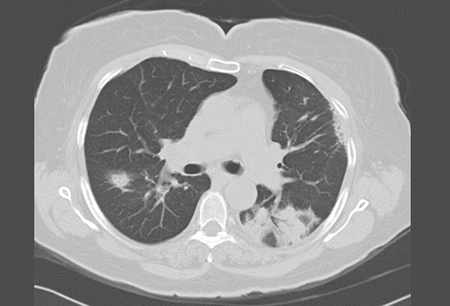

Organising pneumonia

High-resolution chest CT showing bilateral ground glass opacities and a posterior triangular-based infiltrate with an air bronchogram

From the collection of Gary R. Epler, MD